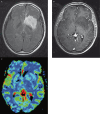

Our goal was to determine whether relative cerebral blood volume (rCBV) can serve as an adjunct to histopathologic grading in the assessment of gliomas, with the hypothesis that rCBV can predict two-year survival. We evaluated 29 newly diagnosed gliomas (13 WHO grade II, seven grade III, nine grade IV; 17 astrocytomas, 12 oligodendroglial tumors). Dynamic susceptibility-weighted contrast-enhanced perfusion MR images and CBV maps were obtained. rCBVmax measurements (maximum tumor CBV/contralateral normal tissue CBV) and progression-free survival (PFS) were recorded. Receiver operating characteristic curves and Kaplan-Meier survival curves were calculated for rCBVmax and histologic grade. rCBVmax measurements differed between gliomas without (2.38 +/- 1.22) and with progression (5.57 +/- 2.84) over two years. The optimal rCBVmax cut-off value to predict progression was 2.95. rCBVmax < 2.95 was a significant predictor of two-year PFS, almost as accurate as WHO grade II. In the pure astrocytoma subgroup, the optimal rCBVmax cut-off value to predict progression was 2.85. In this group rCBVmax < 2.85 was a significant predictor of two-year PFS, an even better predictor of two-year PFS than WHO grade II. rCBVmax can be used to predict two-year PFS in patients with gliomas, independent of pathologic findings, especially in tumors without oligodendroglial components.